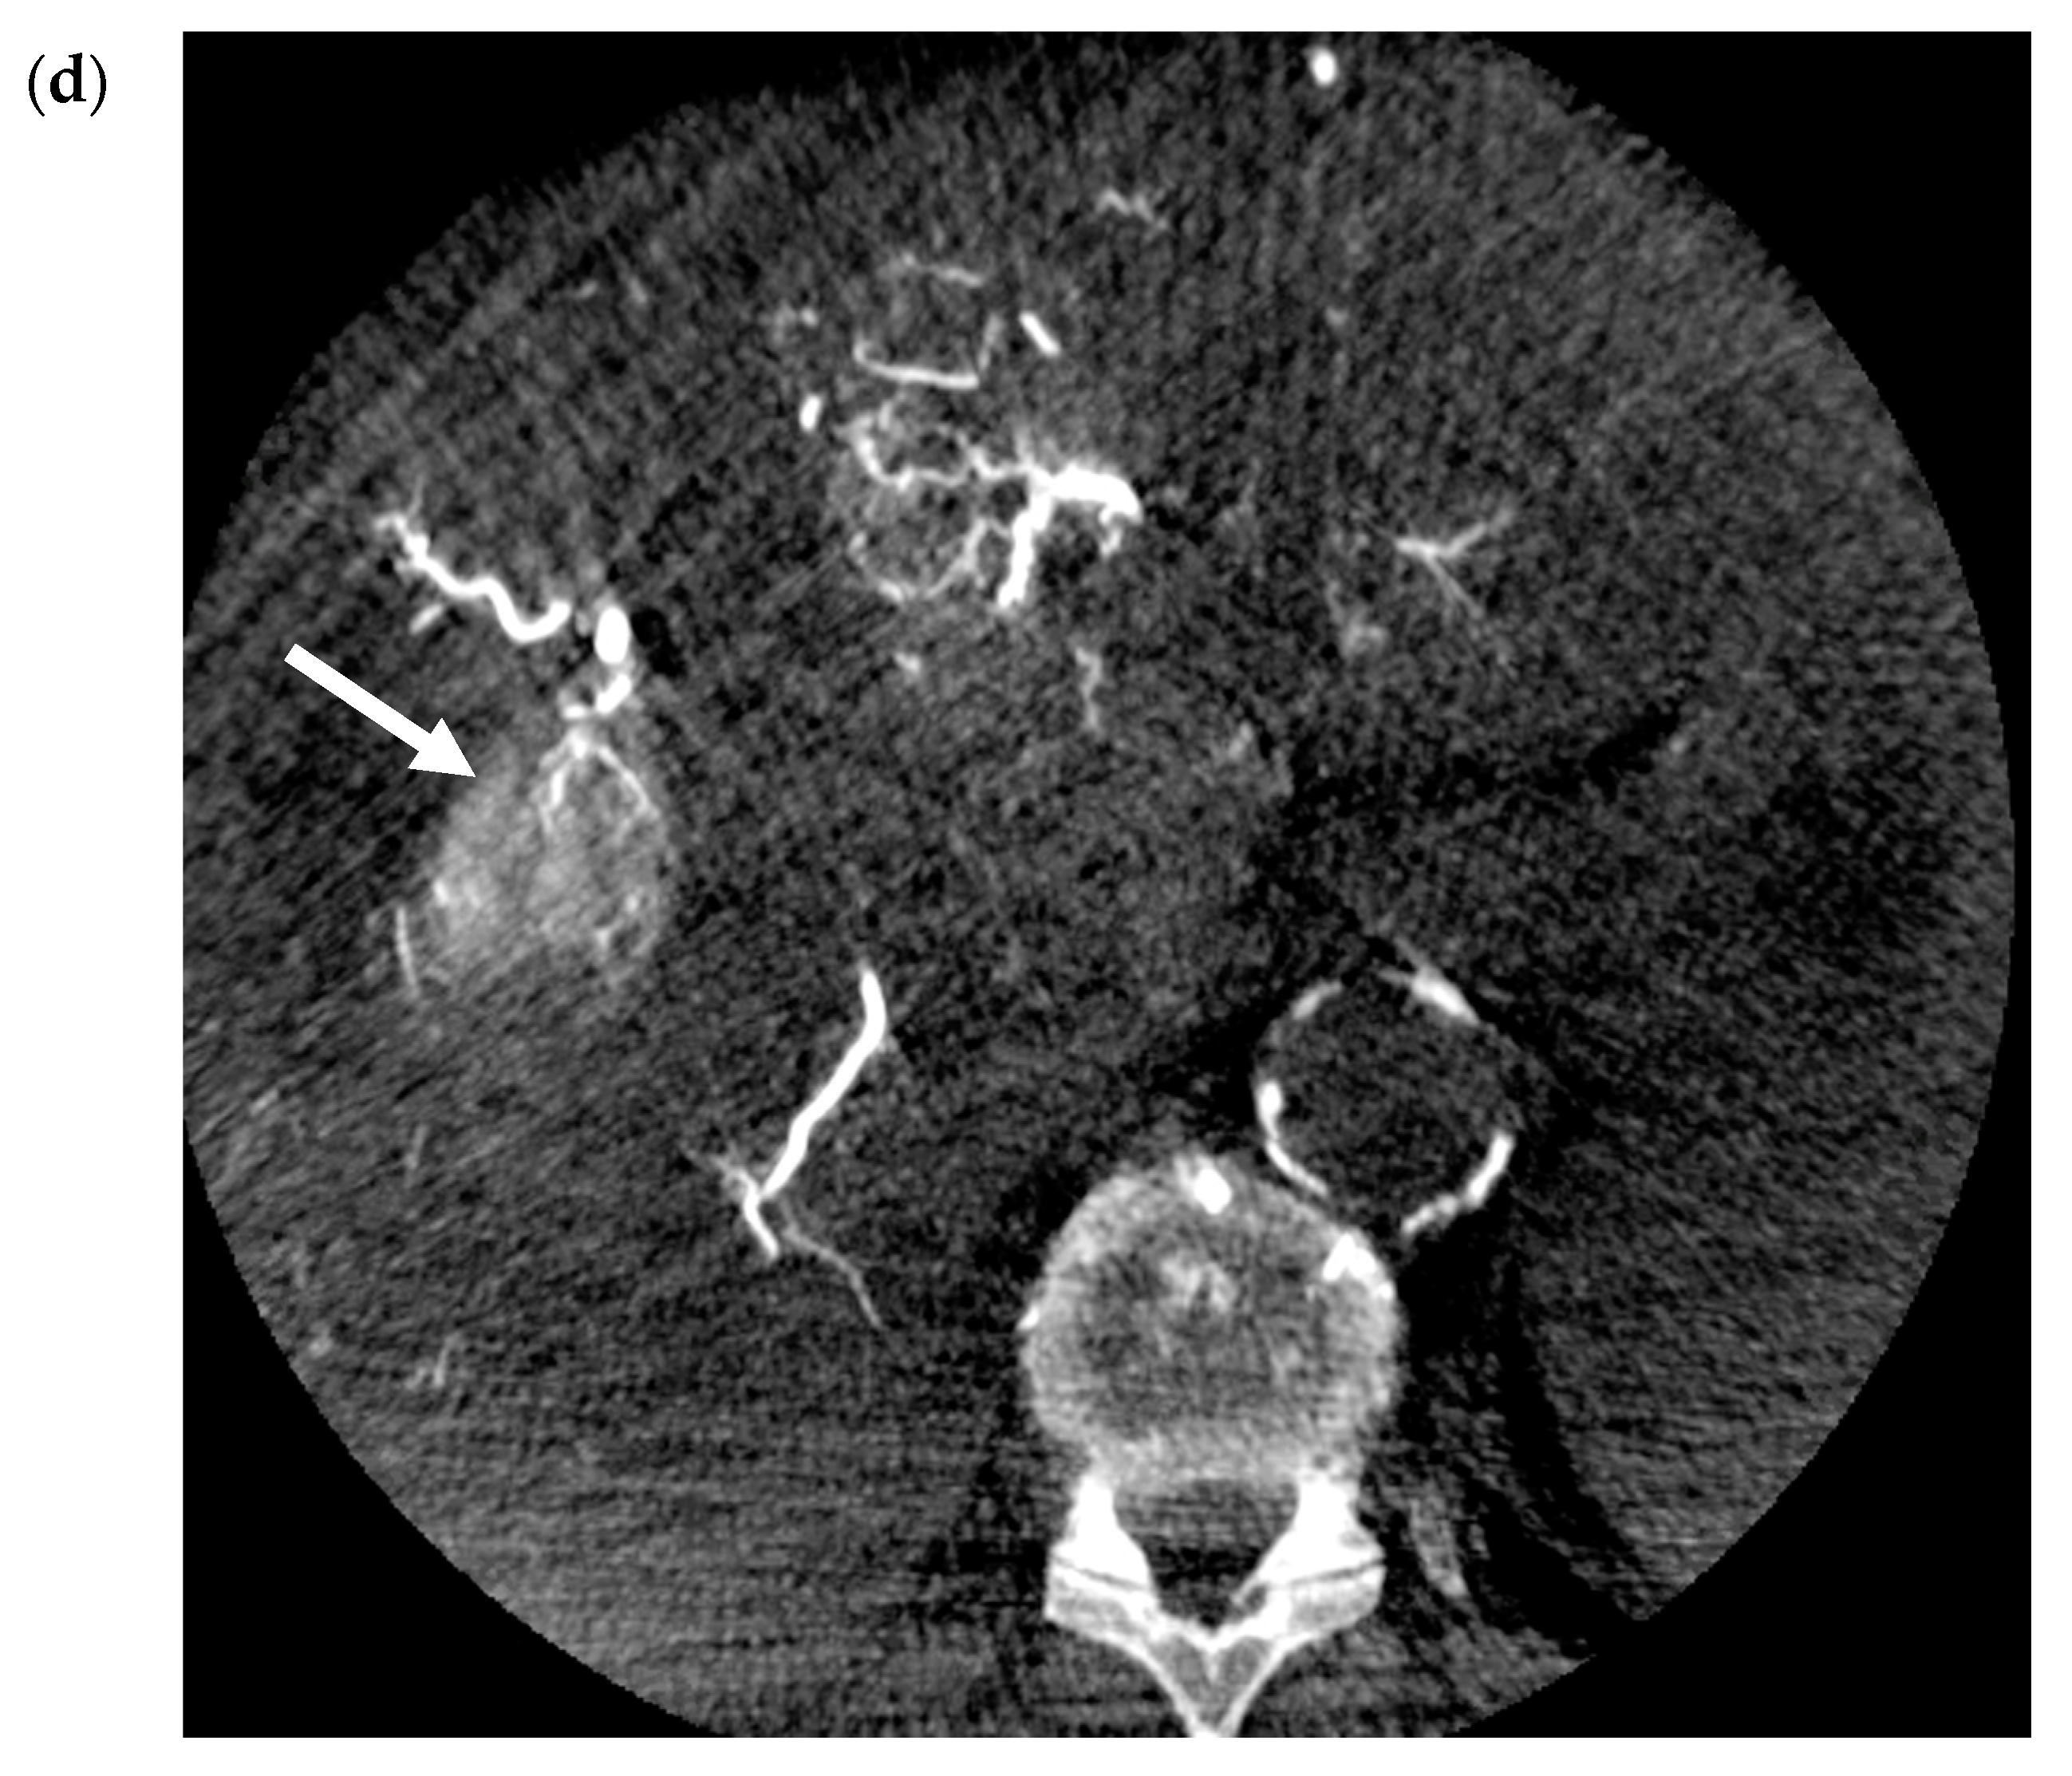

- Riaz, A.; Gates, V.; Atassi, B.; Lewandowski, R.; Mulcahy, M.F.; Ryu, R.K.; Sato, K.T.; Baker, T.; Kulik, L.; Gupta, R.; et al. Radiation Segmentectomy: A Novel Approach to Increase Safety and Efficacy of Radioembolization. Int. J. Radiat. Oncol. 2011, 79, 163–171. [Google Scholar] [CrossRef]

- Padia, S.A.; Kwan, S.W.; Roudsari, B.; Monsky, W.L.; Coveler, A.; Harris, W.P. Superselective Yttrium-90 Radioembolization for Hepatocellular Carcinoma Yields High Response Rates with Minimal Toxicity. J. Vasc. Interv. Radiol. 2014, 25, 1067–1073. [Google Scholar] [CrossRef] [PubMed]

- Lewandowski, R.; Gabr, A.; Abouchaleh, N.; Ali, R.; Al Asadi, A.; Mora, R.; Kulik, L.; Ganger, D.; Desai, K.; Thornburg, B.; et al. Radiation Segmentectomy: Potential Curative Therapy for Early Hepatocellular Carcinoma. Radiology 2018, 287, 1050–1058. [Google Scholar] [CrossRef]